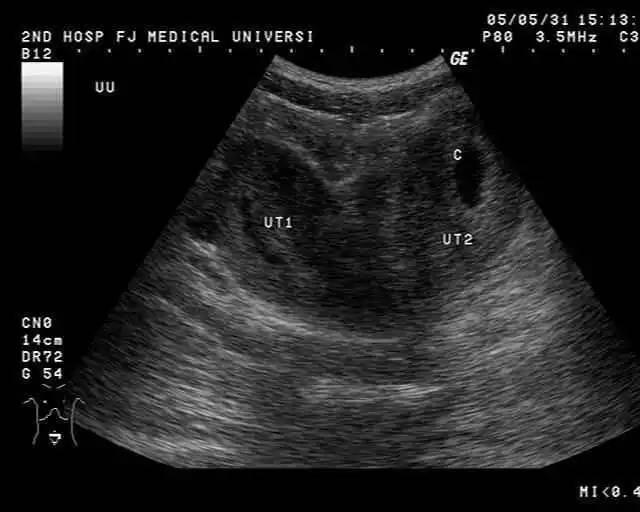

波波,已经怀孕7个多月了,今天,她跟着老公一起去医院做四维彩超,结果医生在检查的时候摇摇头对波波说宝宝是畸形。波波怎么也不相信,还怀疑医生检测有问题。结果医生怒了,斥责丽丽有问题不反省还怪别人,说去哪里检查都一样。波波只有接受了现实,并问医生为什么会导致这样。